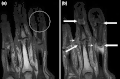

T1 weighted axial MRIs of the fingers in PsA. (a) Pre- and (b) post-contrast showing dactylitis due to flexor tenosynovitis at the second finger with enhancement and thickening of the tendon sheath (large arrow), and synovitis at proximal interphalangeal joint (small arrow). -

Coronal T1-weighted MRI of fingers in PsA. (a) Pre- and (b) post-contrast showing active synovitis at proximal and distal interphalangeal joints (large arrows), joint space narrowing, bone proliferation at proximal interphalangeal joint, erosions at distal interphalangeal joint (white circle), enthesitis medial to proximal interphalangeal joints. -